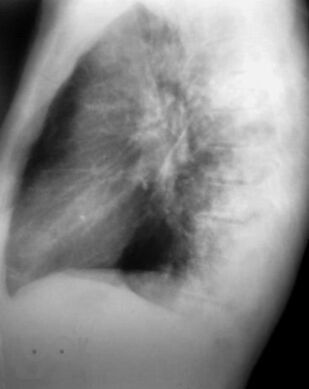

Книга профессора П.В. Власова посвящена современному состоянию лучевой диагностики заболеваний органов грудной полости. Она является первой в отечественной литературе крупной работой, в которой освещена диагностика заболеваний органов грудной полости: острых пневмоний и плеврита, хронических неспецифических заболеваний легких, туберкулеза органов дыхания, рака легкого, опухолей плевры, диффузных и диссеминированных процессов легких, опухолей и кист средостения. Все вопросы рассматриваются с учетом самых современных взглядов на патогенез и диагностику заболеваний.

Большим достоинством книги является комплексный подход к диагностике заболеваний. Наряду с традиционными методами ретгенологического исследования, такими как рентгенография и линейная томография, в книге получили полное освещение роль и место в современном комплексе диагностических средств такие методы, как компьютерная томография и ультрасонография, значительно расширившие возможности диагностики заболеваний.